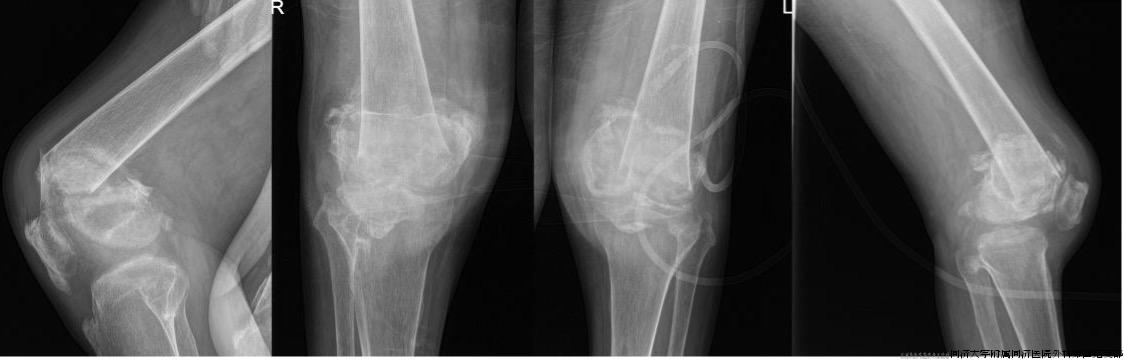

63岁的辜先生是一位沪上“985”大学的教授,15年前一场突如其来的车祸引起颈椎外伤并导致部分瘫痪,从此无法正常行走,但双下肢尚能站立给了他最后的安慰,让他走出了绝望。但3个月前,噩运再次降临:在进行康复运动的时候,辜老师不幸摔倒,双侧膝关节明显畸形,当地医院诊断为双侧股骨远端严重粉碎性骨折(图1)。由于长时间卧床所致的极严重骨质疏松及长久肺炎所致的呼衰让骨科和麻醉科医师都望而却步。带着畸形的双侧膝关节,他辗转沪上多家大医院未果。失望之际,他带了一丝期许慕名来到上海市同济医院,骨科副主任、创伤骨科主任樊健教授分析病情后,决心勇挑重担,帮助辜老师实现能站立的愿望。

图1.术前X线:双侧膝关节结构紊乱